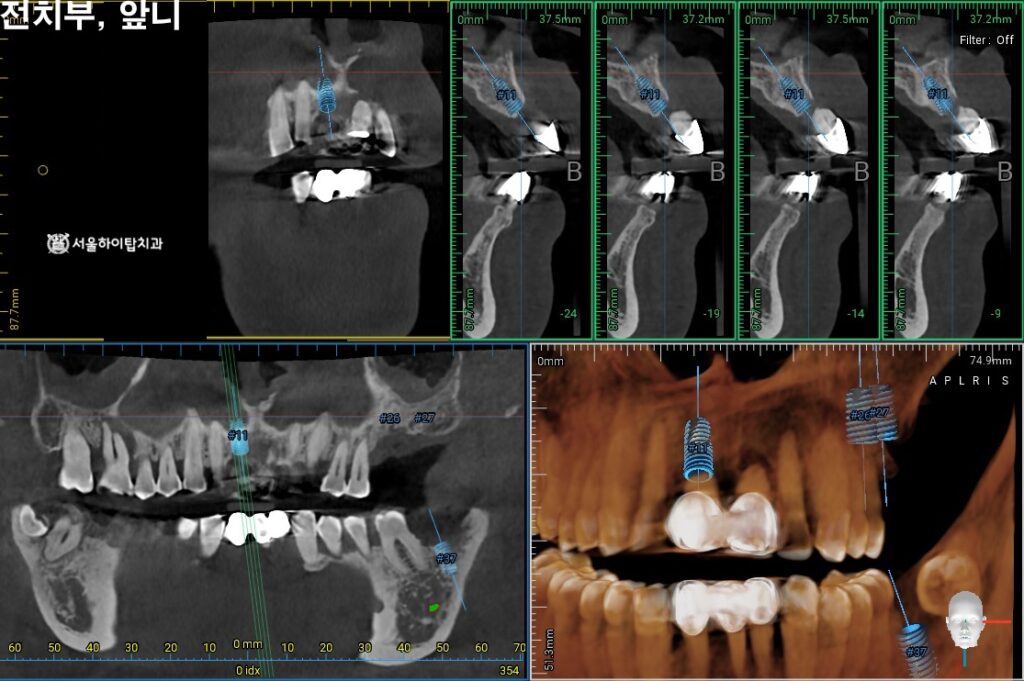

2. 정밀한 3D-CT 검진

구치부는 어금니가 상실되어 있고,

앞니의 경우 치주 지지력이 부족해

동요도가 심한 상태이므로

임플란트가 필요한 상황입니다.

이에 따라 정밀 CT 촬영을 통해

임플란트가 식립될 위치와 각도를

사전에 시뮬레이션할 수 있습니다.

이 과정에서,

치조골의 폭과 높이,

해부학 구조(상악동, 신경 등)와의 거리,

임플란트 지지력 확보를 위한 골질 상태

등을 면밀히 확인할 수 있으며,

이를 기반으로 가장 안정적이고

예측 가능한 계획을 세우게 됩니다.

현재 위턱의 경우는

골 소실이 심하기 때문에

GBR, 즉 뼈 이식이 함께

병행될 것으로 보여집니다.

이어서 앞니의 경우에도

사전 시뮬레이션을 진행하여

알맞은 위치와 각도를 결정합니다.